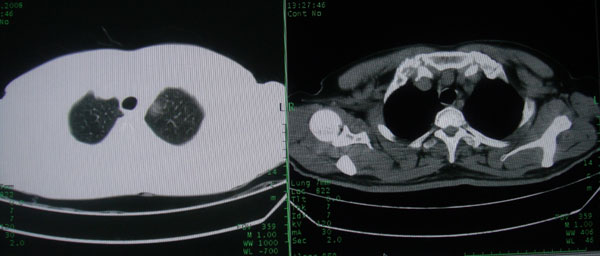

患者男性58岁因二周前起咳嗽,今天胸片示左上肺占位性病变行ct检查,无发热,无咯血痰.

左上肺感染性病变,结核伴空洞形成可能,左上肺膨胀不全

左肺上叶病灶,实变但见含气支气管、空洞但未见壁内结节及积液;

考虑:①感染性病变(包括特殊感染型肺tb)

②肿瘤性病变(考虑患者年龄比较大的关系/所以不排除)

初学者。。。左肺空洞性病变,并可见阻塞性肺不张改变,鉴于患者为老年男性,且临床症状仅有咳嗽,全身中毒症状不明显,所以我首先考虑为左肺癌性空洞并左侧肺门淋巴结转移伴左肺阻塞性肺不张。结核性空洞放于第二位考虑,可以进行相关实验室检查。希望能有病理结果,谢谢!!!!!

左肺上叶实变影,内见支气管充气征及空洞影,病人年龄较大,无发热及结核中毒症状,心影左移,未见纵隔淋巴结肿大;不知实验室检查结果如何?有否嗜酸细胞增多,有没有进行治疗?就目前资料首先考虑1.感染性病变,2.慢性嗜酸性肺炎?可结合实验室检查并短期治疗复查,肺癌不能排除。